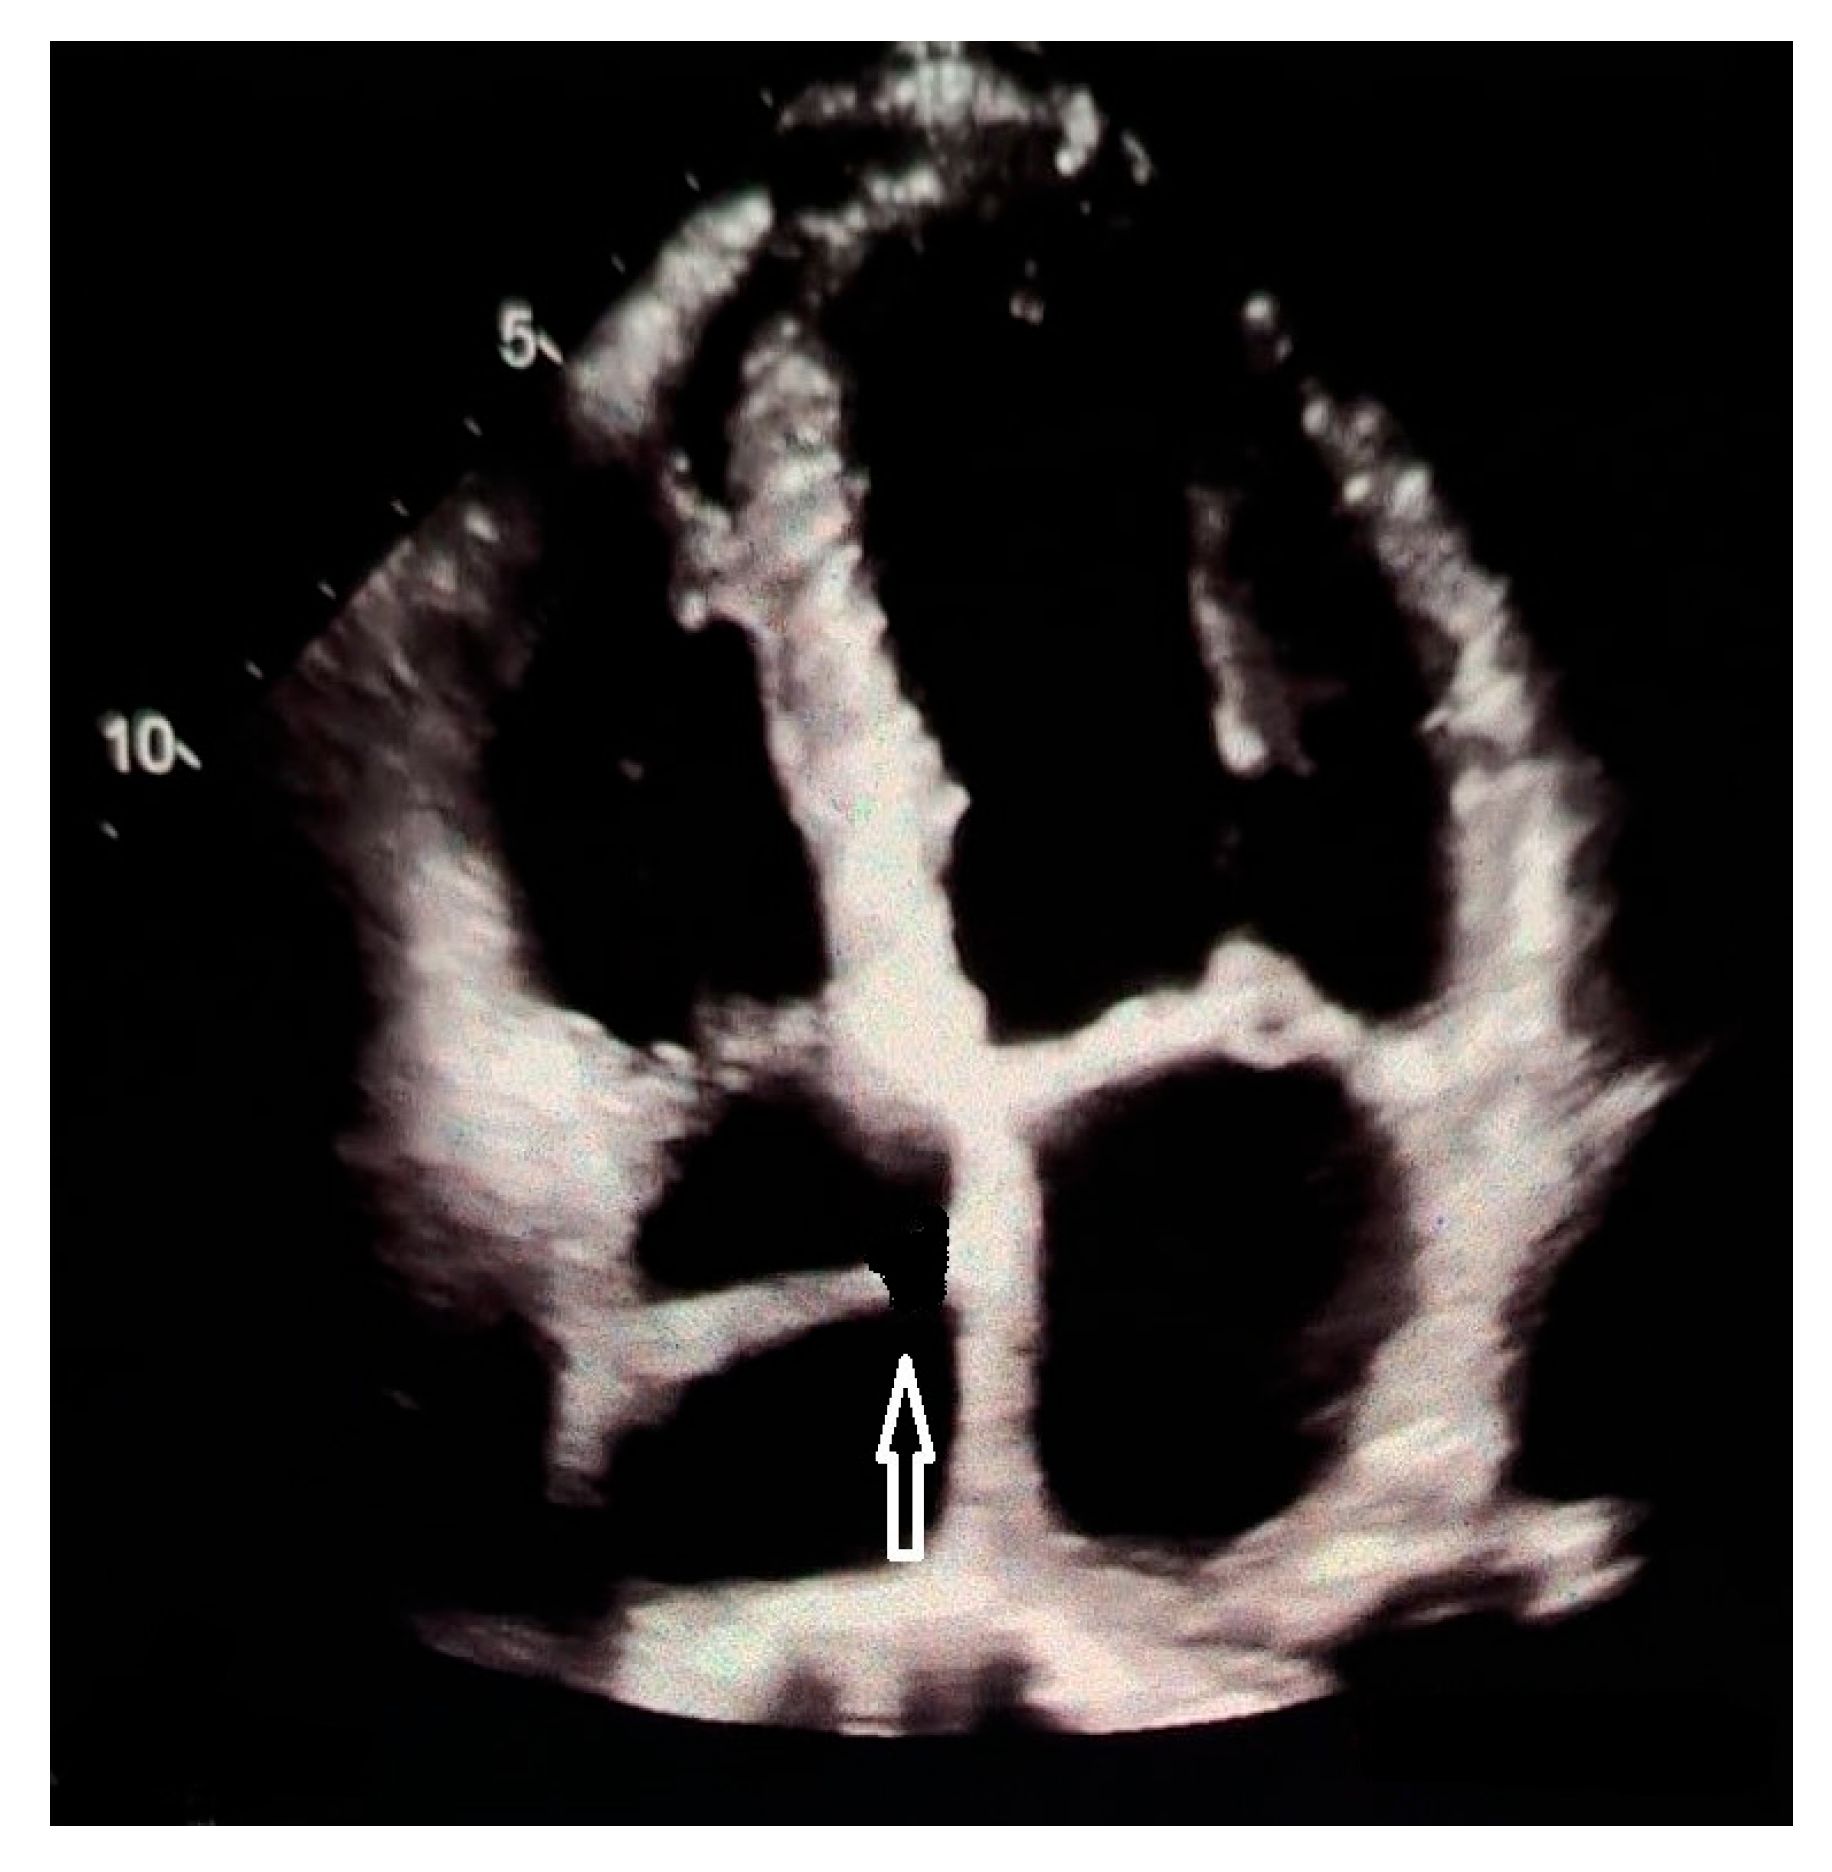

- Yamaguchi, R.; Ota, T.; Tanigawa, T.; Sakai, M.; Norioka, N.; Ishikawa, S.; Kawai, K.; Nishiyama, H.; Tsumori, T.; Kamimori, K.; et al. Cor Triatriatum Dexter with Atrial Septal Defect Evaluated by Real-Time Three-Dimensional Transesophageal Echocardiography. J. Echocardiogr. 2013, 11, 77–79. [Google Scholar] [CrossRef]